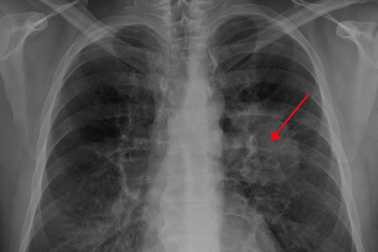

Phương pháp bất ngờ cứu bệnh nhân ung thư chỉ trong 1 tuầnViện Ung thư London (Anh) vừa công bố một liệu trình điều trị mới dựa trên xạ trị truyền thống giúp việc chữa trị ung thư phổi, ruột, vú và tuyến tiền liệt...được hiệu quả hơn.